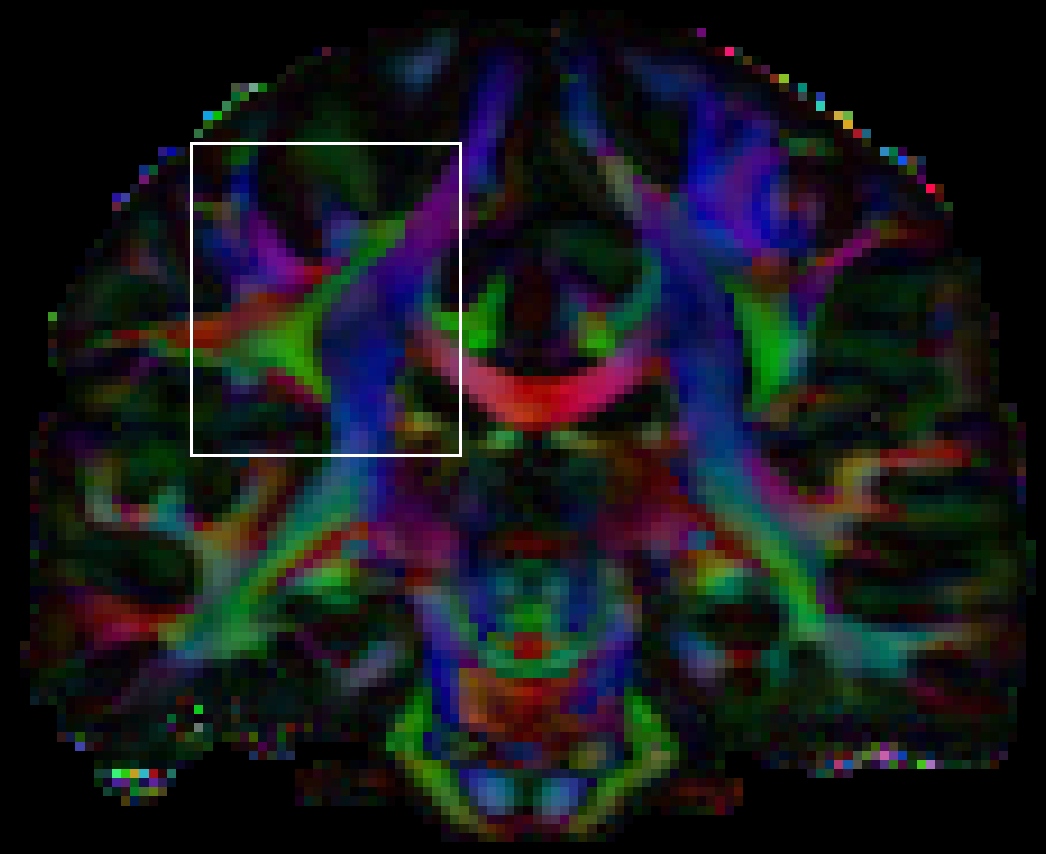

The in vivo data set was taken from the Human Connectome Project (HCP) database.333See https://ida.loni.usc.edu and the Acknowledgments section. The data set consists of each 90 diffusion weighted images for -values , and . Of these, we only used the points. As the data set is intended primarily for brain research, not for evaluating reconstruction and tracking methods, its SNR is rather high, so that even unregularized reconstructions show a good spatial coherence. Still, it is interesting to test the performance the CSD-FC method on this data set, in particular to see how well the geometric assumption of locally straight fibers is fulfilled in a realistic situation. Therefore, the spatial regularization parameter was deliberately chosen rather large to highlight some of its strengths and shortcomings.

Reconstructions were performed on a voxel subset of the volume around the area shown in figure 4. We parametrized the convolution kernel as an exponential function, , with parameters obtained from a previous DTI reconstruction by averaging the sorted eigenvalues of all tensors with fractional anisotropy (FA) exceeding a certain threshold and taking the mean value of the smaller two eigenvalues in order to obtain an axially symmetric kernel. Instead of an unregularized reconstruction for comparison, we used a small penalty. Visual inspection showed that this did not have significant impact on the resolved structures. However, it increased FA contrast by reducing noise in empty areas and, more importantly, lead to ODFs that are slightly broader and can therefore be depicted in printed plots more clearly.

Reconstruction results for two slices are shown in figures 5 and 6. For brevity’s sake, we only compare the -penalized reconstruction to the CSD-FC+LB method.

The top of figure 5 shows a rather complicated “kissing” fiber structure. As in the phantom data set above, the FC penalty tends to introduce spurious crossings in the sharply bent part, which can also be seen in the top highlighted region. The bottom highlighted region counter-intuitively shows a reduced quality of the resolved crossing structures. We observed the same effect with spatial regularization alone, without the Laplace-Beltrami penalty. The reason for this observation is not clear.

For the slice in figure 6, the highlighted region at the bottom shows a straight elongated structure, the coherence of which is significantly improved by the FC penalty. The other region shows a white matter structure extending into a gray matter area, which may or may not be an artifact due to the general tendency of the penalty to prolong elongated structures. In cases like these, validation based on other sources of knowledge about the local structures is necessary.

A notable feature of the regularized reconstructions is the significantly improved FA contrast between gray and white matter. In the figures shown, this might be attributed to the Laplace-Beltrami penalty. However, we observed the same effect with spatial regularization alone, i.e. the spatial penalty is able to distinguish between noisy and oriented structures using the fact that the former are not coherent with their surroundings.